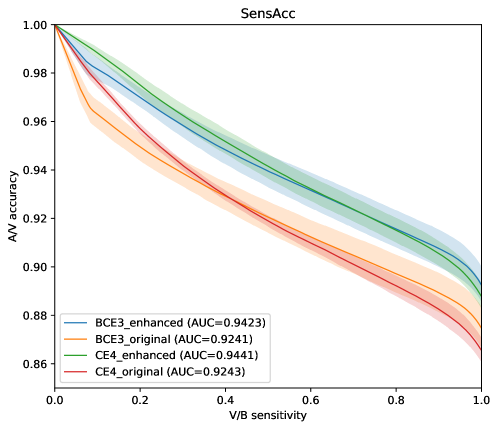

In Figure 8, the mean ROC and PR curves in RITE-test for the networks that were trained using the BCE3 and CE4 losses with and without image preprocessing (“enhanced” and “original”, respectively) are depicted.

Complementing the segmentation results, Figure 10 depicts the ROC and PR curves of the different approaches for the A/V classification in the RITE-test set. These curves are built considering only the pixels labelled as “vessel” in the ground truth, being “artery” the positive class.

Figure 12 depicts the vessels classification sensitivity against the artery/vein classification accuracy of the different models and multiple thresholds in RITE-test dataset.

As it can be observed in the vasculature segmentation results of Figures 8 and 9 as well as Table 2, the best performance is achieved by the proposed MS approach using the BCE3 loss, either using the enhanced or the original retinography as input, and regardless of the target class. For each structure of interest, i.e. arteries, veins and vessels, both the AUC-ROC and AUC-PR values are higher with the MS approach than with the traditional CE4 one. Furthermore, AUC-PR and AUC-ROC for vessels are significantly higher for the MS approach than for CE4 (), as well as other statistics like AUC-ROC for arteries () and AUC-ROC por veins ().

Regarding the artery/vein discrimination, although the MS alternatives achieve highly positive results (see Table 3), it cannot be affirmed that they perform better than the traditional alternatives. Considering the variability, the A/V classification results of both approaches are not significantly different. However, for the vessel/background discrimination, the situation is different. In this case, consistently with the higher AUC values for vessels segmentation, the MS approach achieves significantly better results () for both Accuracy and AUC-ROC. As can be seen in Table 3, when training with the original images, the sensitivity values of the MS approach are, on average, more than 2.5% higher than those of the traditional approach. Similarly, when training with the enhanced images, the improvement is about 1%. We focus on sensitivity, at a similar level of specificity, due to the positive class that is “vessel”, and the sensitivity measures the proportion of positives that were correctly identified. Specificity and accuracy, although they are also relevant, are much less sensitive in this scenario, since they take into account the background pixels, much more numerous and easier to classify.

The results depicted in Figure 12 are also in this line. Both methods, the traditional CE4 loss and the proposed MS with BCE3 loss, perform similarly when evaluated in simultaneous vascular segmentation and artery/vein classification. It is remarkable, however, that for a high vascular segmentation sensitivity the proposed approach achieves a slightly higher artery/vein classification accuracy.

In light of all these results together, it can be stated that the MS approach represents the more convenient alternative, since it is able to detect more vessels with similar A/V classification accuracy.